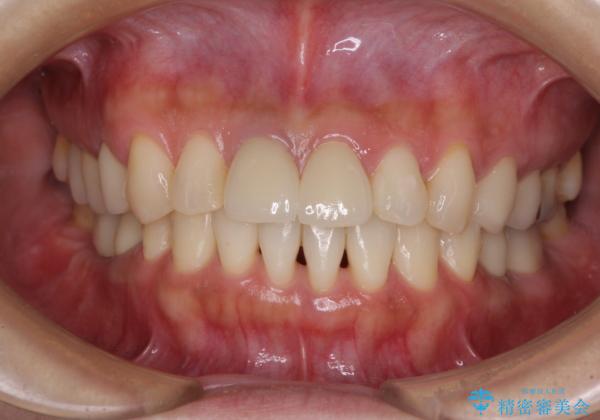

治療途中より、上の歯や反対側の銀歯、上顎前歯の色合いや下顎前歯のデコボコが気になってきたため、全てを治療することとしました。

仕事が多忙な方で、来院間隔が開いてしまうことが多く、治療期間はかかりましたが、来院回数は最小限で終えることができました。